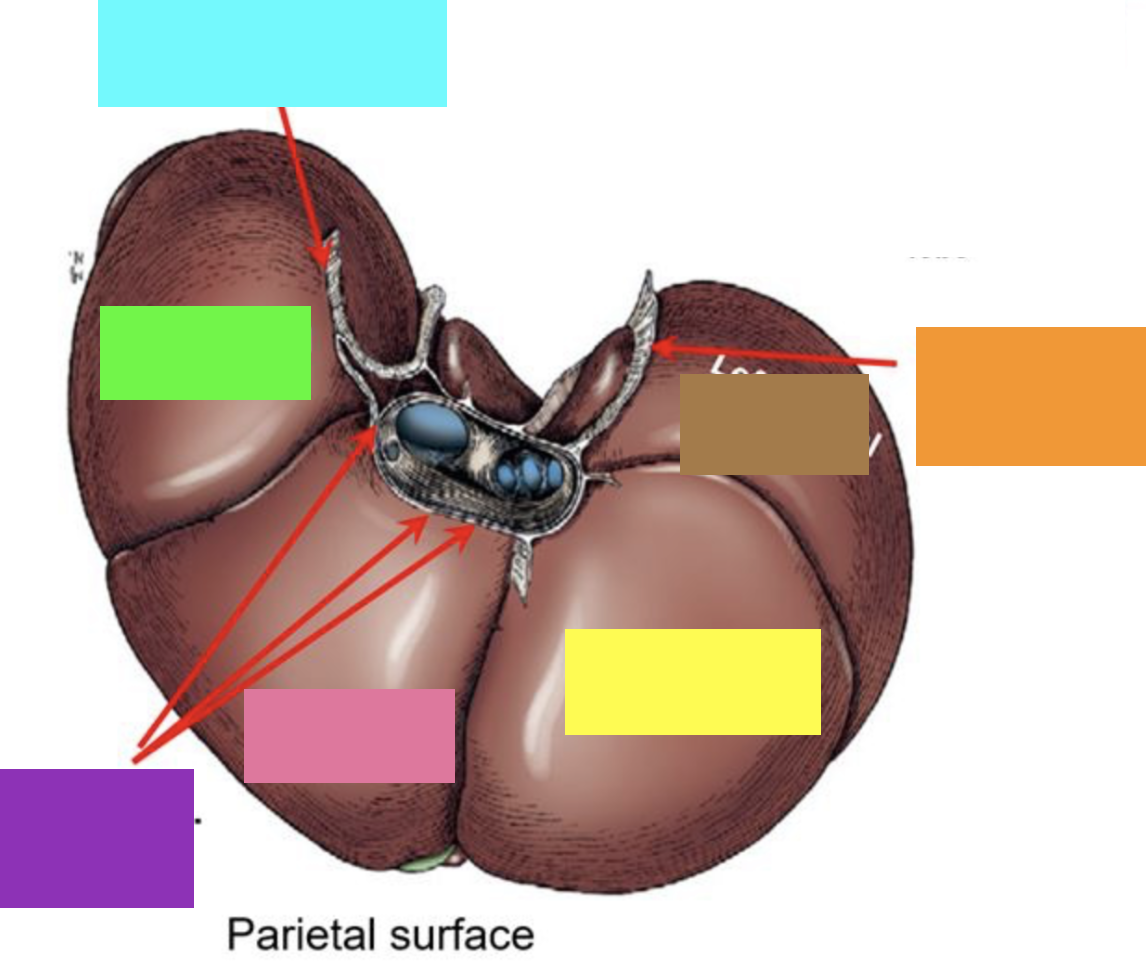

blue box

right triangular ligament

green box

right lateral lobe

purple box

coronary ligament

pink box

right medial lobe

yellow box

left medial lobe

orange box

left triangular ligament

brown box

left lateral lobe